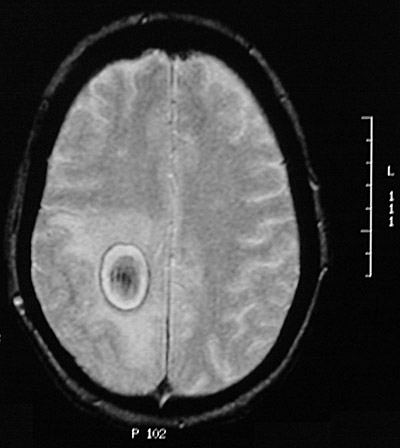

| This is an organizing hematoma in the parietal lobe seen with a T2 weighted MRI scan in axial view. It is distinguished from an abscess because the center is not bright from liquid contents. It is distinguished from a neoplasm by the dark rim representing hemosiderin deposition and the dark center with the blood products. A necrotic center would be white on a T2 weighted scan, more typical for a neoplasm with central necrosis or an abscess. There is some surrounding edema. |